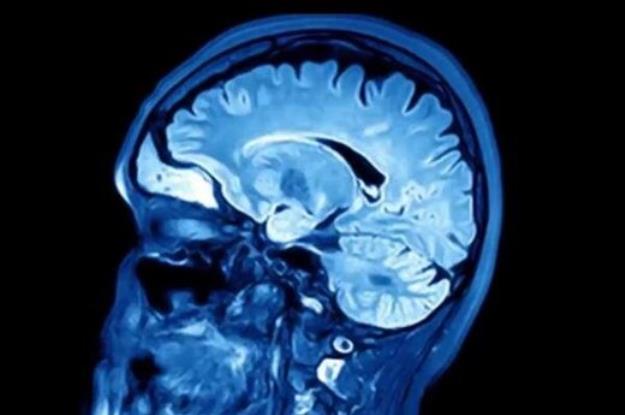

آلزایمر شایعترین نوع زوال عقل است. یکی از مهم ترین دلایل بروز آلزایمر، تجمع پلاکهای پروتئین آمیلوئید در مغز است. آمیلویید یک اصطلاح عمومی برای پروتئینهایی است که به طور طبیعی در بدن بوجود میآیند. در مغز افراد سالم، این پروتئین نابود میشود ولی در مغز افراد مبتلا به آلزایمر، تجمع مییابد.